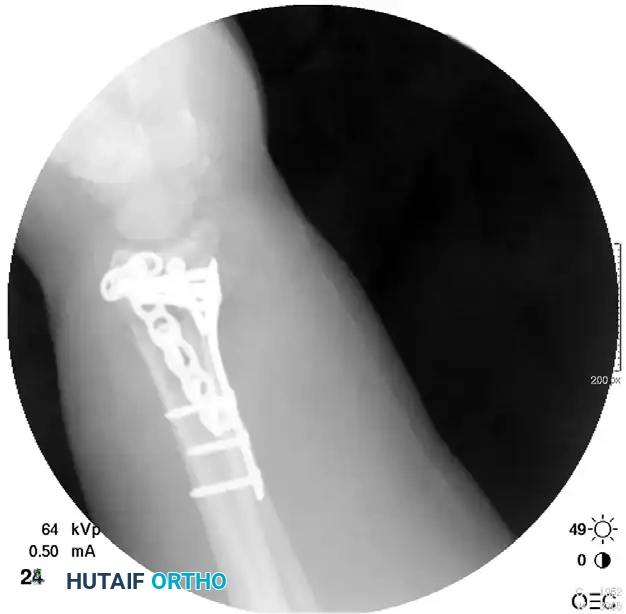

The following sequence demonstrates a highly comminuted distal radius fracture successfully managed with a dorsal distraction plate:

Initial Injury Radiographs:

Postoperative Fixation with Distraction Plate:

Associated Surgical & Radiographic Imaging